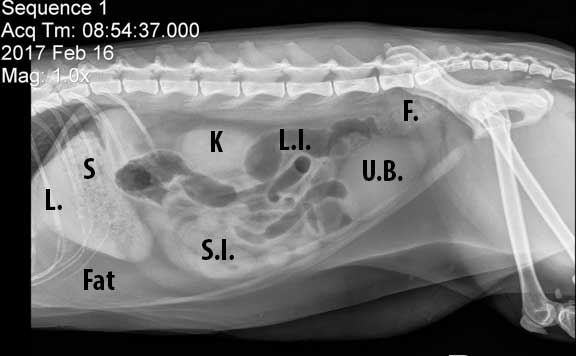

Learn How to Read a Cat X ray Long Beach Animal Hospital

Learn How to Read a Cat X ray Long Beach Animal Hospital

Radiographs of the cat normal anatomy vet Anatomy